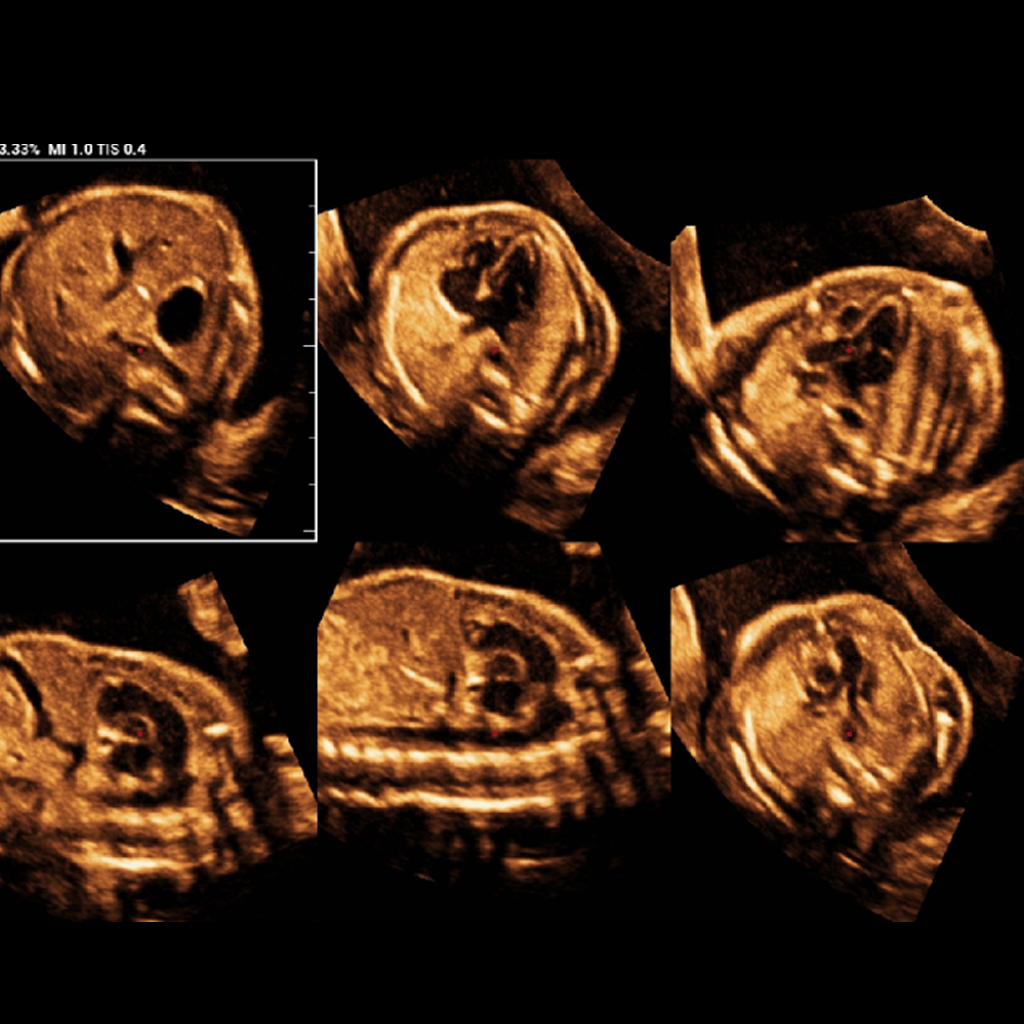

Автоматизирано идентифициране на стандартни сърдечни участъци на плода, подкрепено от обширна база данни за подобряване на възможностите за самообучение на системата за изкуствен интелект. Рационализирано извличане на шест стандартни изгледа на сърцето на плода за опростен анализ.